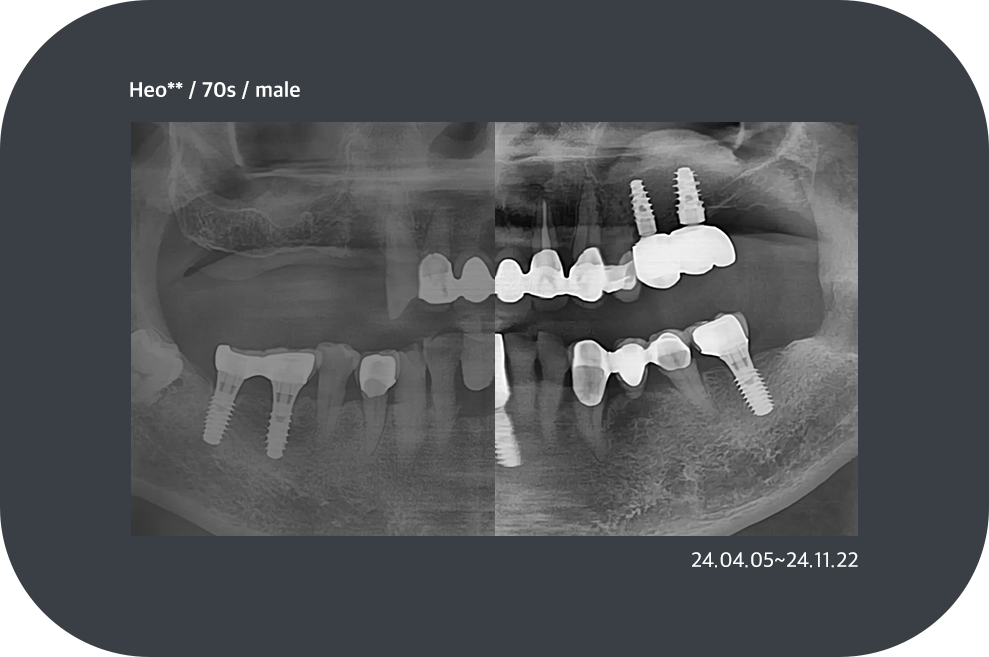

치료사례

임플란트 치료사례

*모든 증례 사진은 의료법 제23조, 제56조에 의거하여, 당사자의 동의하에 게시하였습니다.

*치료 사진은 모두 본원에서 치료한 환자분의 사진입니다.

*치료 사진은 모두 동일인의 사진이며, 동일조건에서 촬영하였습니다.

*개인의 차이에 따라 시술 및 수술 후 부작용이 발생할 수 있으며, 의료진과 충분한 상담을 받으시기 바랍니다.